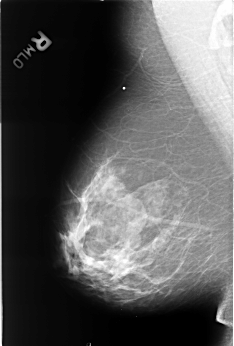

B_3247_1.RIGHT_CC

RIGHT_CC LINES 4424 PIXELS_PER_LINE 3040 BITS_PER_PIXEL 12 RESOLUTION 50 NON_OVERLAY